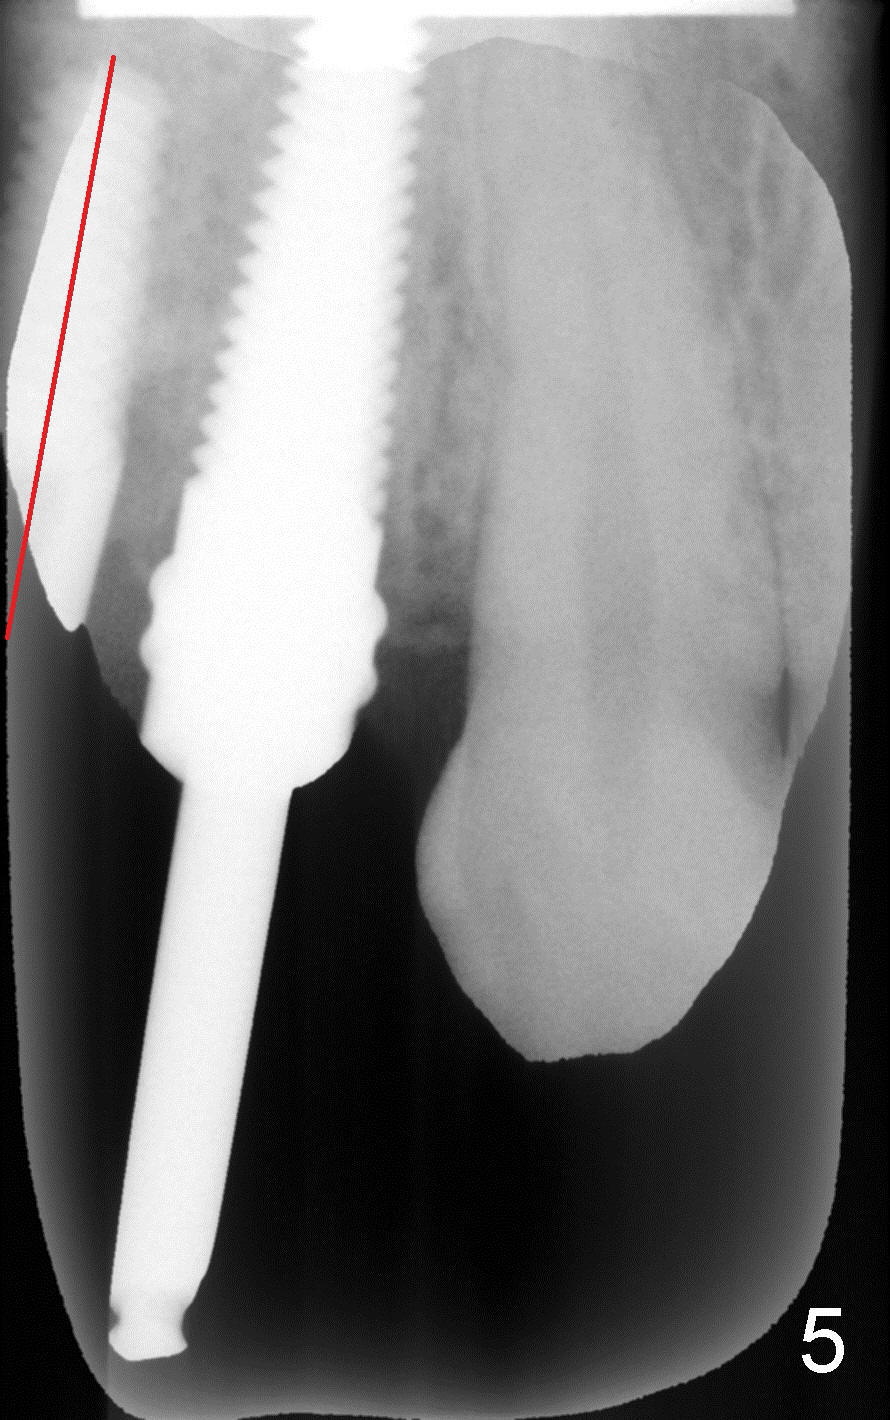

8. 4.5x17 tap, implants, torque wrench (4.5x11 and 4.5x14 mm tapered implants were placed at the sites of #4 and 5, respectively (Fig.6))

9. Fig.2,3 show pilot drill and guiding pin at the sites of #4 and 5, respectively.  Thanks to our joined effort, the axis of the implant at the site of #4 was corrected from Fig.4 to 6